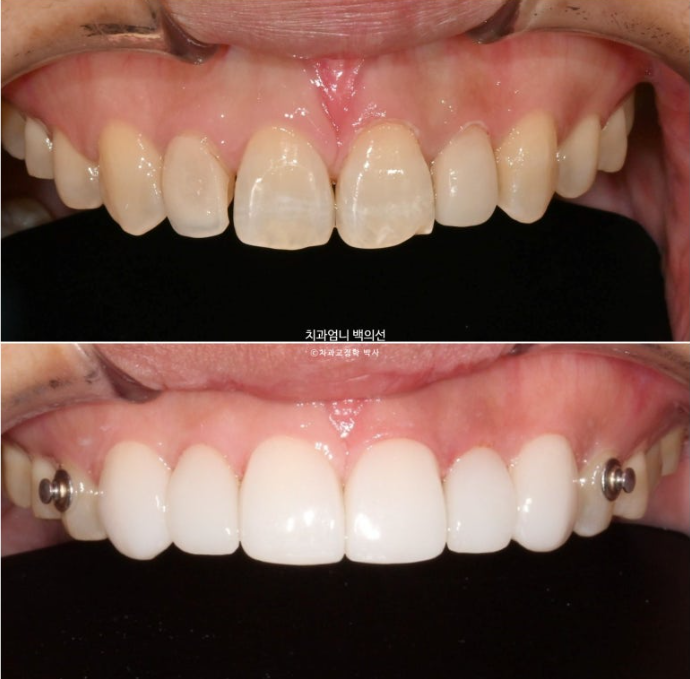

23.05~25.05

이제 전후비교 보겠습니다.

개방교합이 해소가 되었으니 이제 음식을 앞니로 베어드실 수 있게 되었습니다.

뿐만아니라 하관이 짧아지는 효과도 보실 수 있습니다.

2년간의 치료결과 중첩을 해보면 어금니가 3mm 함입되었고 앞니가 위 아래 각각 1mm씩 정출이 되어 개방교합이 완전히 해소되었습니다.

함입된 어금니 덕에 아래턱이 더 다물리며 자가회전이 일어나서 하관이 짧아졌습니다.